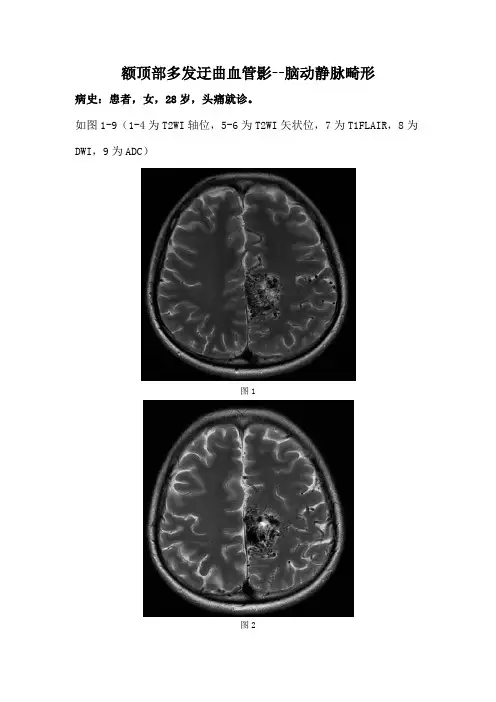

额顶部多发迂曲血管影--脑动静脉畸形病史:患者,女,28岁,头痛就诊。

如图1-9(1-4为T2WI轴位,5-6为T2WI矢状位,7为T1FLAIR,8为DWI,9为ADC)图1图2图3图4图5图6图7图8图9 基础解剖影像:图10图11图10-11所示为正常颅脑T2WI轴位及T1WI矢状位,可见半卵圆中心(绿色箭头)、大脑镰(蓝色箭头)、胼胝体(棕色箭头)、小脑扁桃体(白色箭头)。

图1图2图3图4图7图1-4所示T2WI轴位及图7T1WIFLAIR轴位可见大脑镰旁多发粗细不等血管流空信号影(棕色箭头),其中一条粗大静脉血管影(绿色箭头)向上走行至上矢状窦内(黄色箭头)。

似见细小流空血管影(白色箭头)汇入血管巢内(棕色箭头),考虑为大脑前动脉胼周动脉分支。

图5图6图8图9图5-6所示T1WI矢状位可见大脑镰旁额叶内多发迂曲粗细不等血管流空信号影。

大脑前动脉胼周动脉分支(白色箭头)呈细小血管流空信号汇入血管巢内(棕色箭头),血管巢上方粗大引流血管流空信号影(绿色箭头)汇入增粗上矢状窦(黄色箭头)。

图8-9所示DWI及ADC可见迂曲血管影,其内见两处点状DWI高信号、ADC高信号,考虑T2透射效应可能。

影像诊断:脑动静脉畸形。

分析思路:本例病变位于幕上脑实质内,可见供血动脉(大脑前动脉胼周动脉分支)、血管巢(多发细小血管)、粗大引流静脉(向上引入上矢状窦),明确诊断脑动静脉畸形。